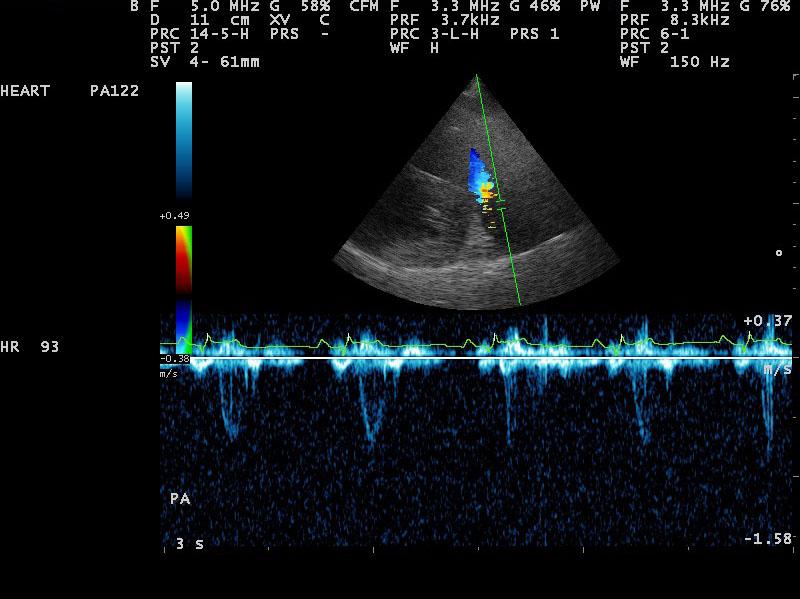

A 10-year-old SF Labrador was presented for evaluation of ascites, which was quantified as a modified transudate. Additional history on this dog was that 11 months prior an ovariohysterectomy and resection of mammary gland tumors had been done. The tumors were benign on histopathology. On abdominal ultrasound, the ascites, hepatic congestion, and a dilated CVC were present.